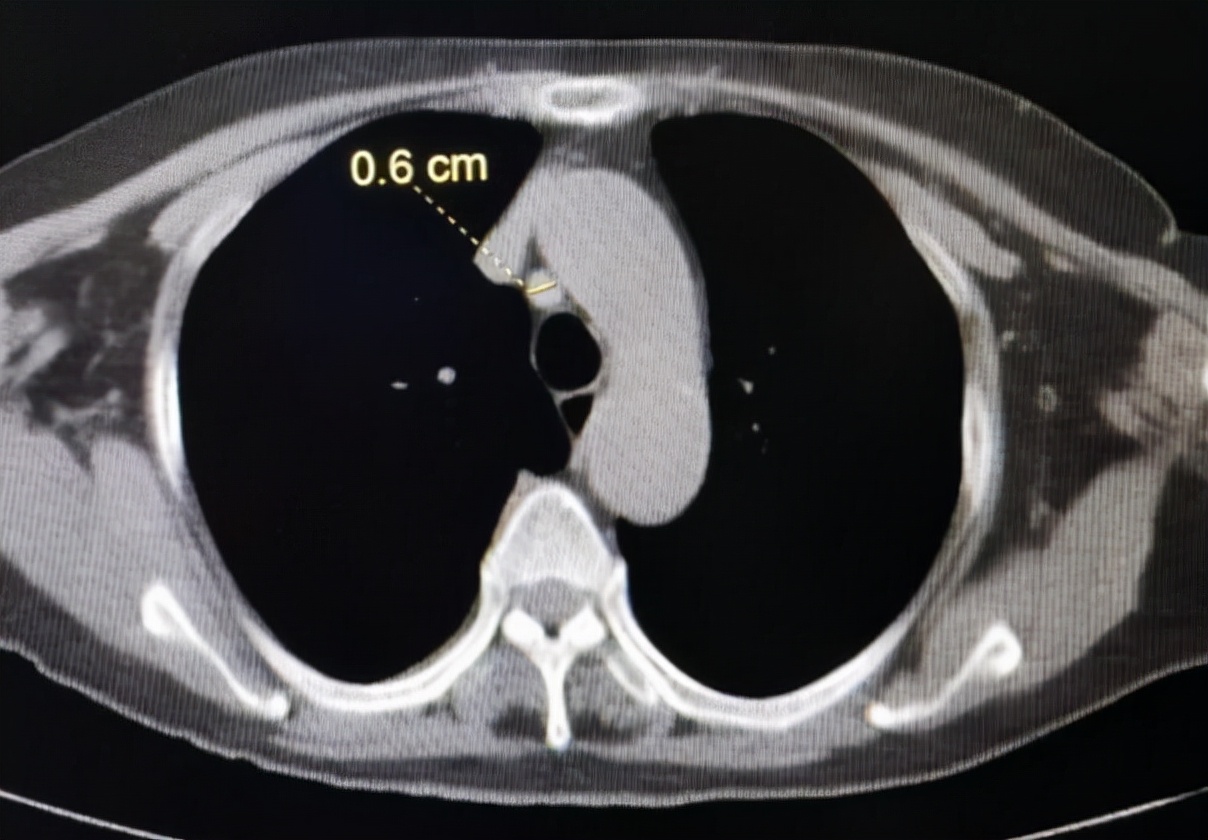

右肺中叶微小结节。需要半年复查

纵隔6mm小淋巴结,边缘光整